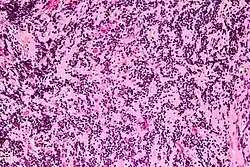

Das Pineozytom ist eine seltene Form eines Pinealoms, eines Tumors der Zirbeldrüse, und entsteht aus den sekretorischen Nervenzellen Pinealozyten.[1][2][3]

Im Gegensatz zum Pineoblastom handelt es sich beim Pineozytom um einen gutartigen Tumor (Grad I WHO). Er ahmt die Grundstruktur der Zirbeldrüse nach und wächst langsam und verdrängend, nicht infiltrierend.[4]